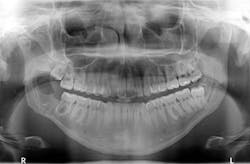

A panoramic was taken, and a large radiolucent lesion was noted to extend from the distal of No. 1 to the distal of No. 32. A significant amount of bone destruction in the mandible was observed. Furthermore, a radiolucency was present distal to the crown on No. 17. Clinically, there was inflamed tissue around partially erupted No. 32 that extended up to the distal of No. 2 (figure 4). The area was tender to palpation and unremarkable extraorally.

Figure 4: Radiograph taken at time of complaint